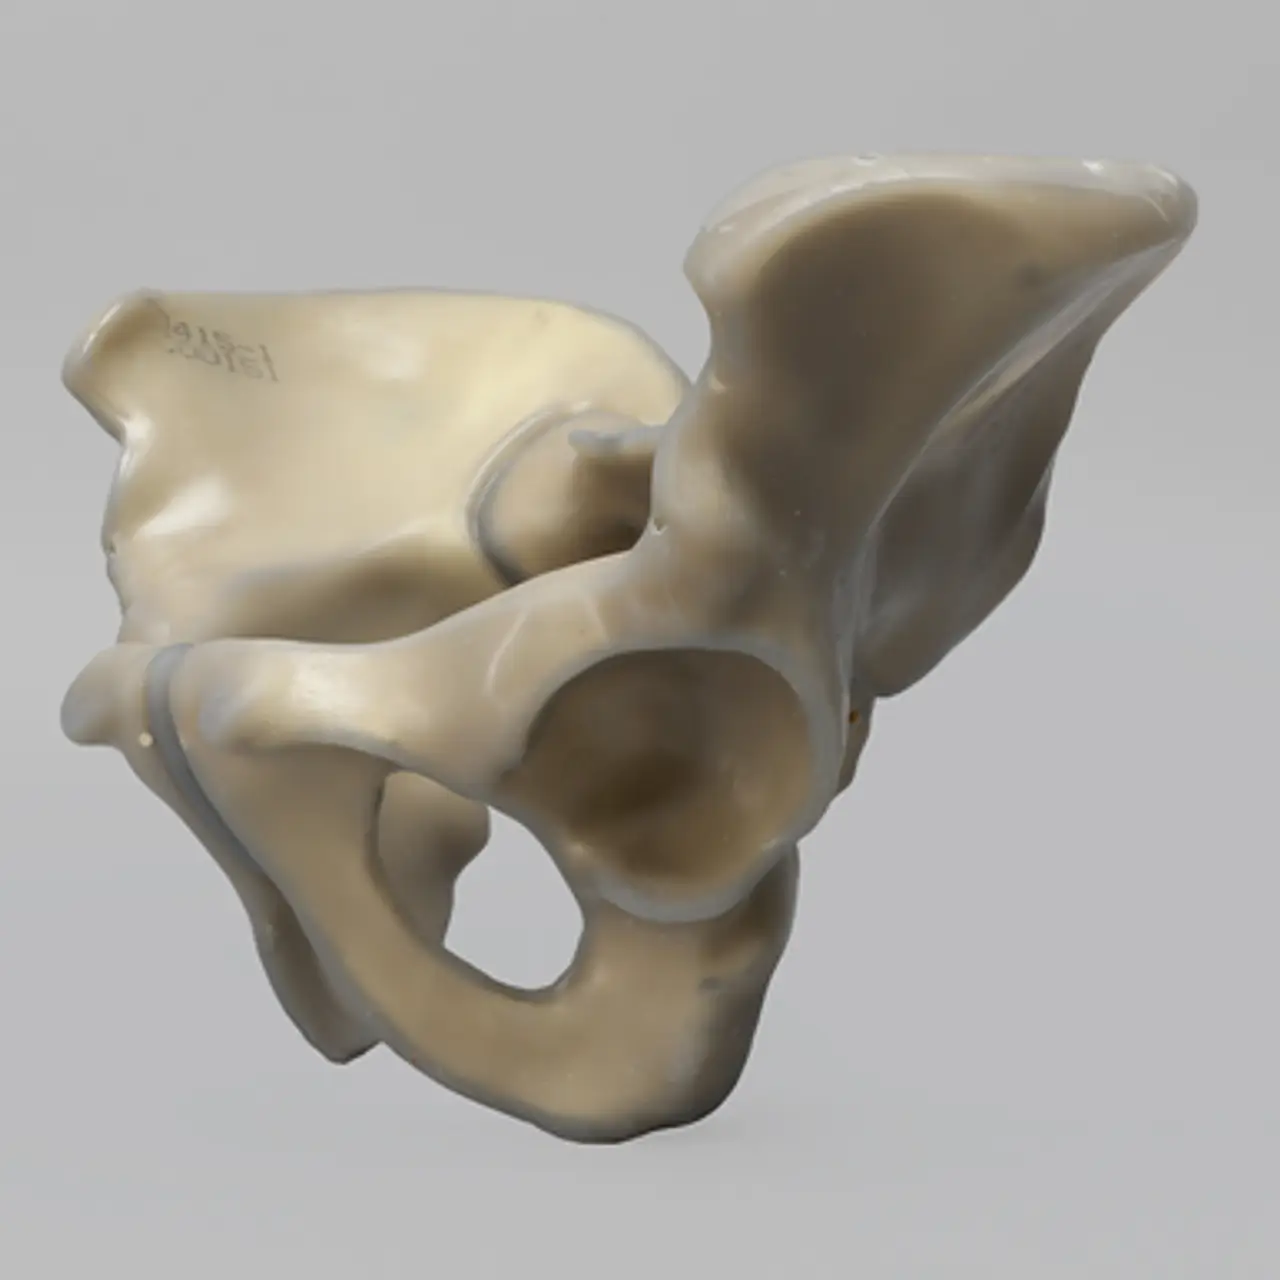

人工骨骨盆模型3415

人工骨模型,完整男性骨盆,absolute™ 第四代,17 PCF 实心泡沫芯,大号

用于力学测试的完整男性骨盆

我们的 absolute™ 骨模型 精确模拟人体骨骼的结构与力学特性,能够帮助科研人员和医疗器械企业在开发与审批过程中,轻松且经济地再现载荷与运动场景。该模型特别适用于生物力学研究、医疗器械测试及教学演示。

| 解剖部位 (Anatomy) | 骨盆 – 完整 |

| 模型类型 (Model Type) | absolute™ 骨模型 |

| 材料 (Material) | absolute™ |

| 尺寸 (Size) | 大号 |